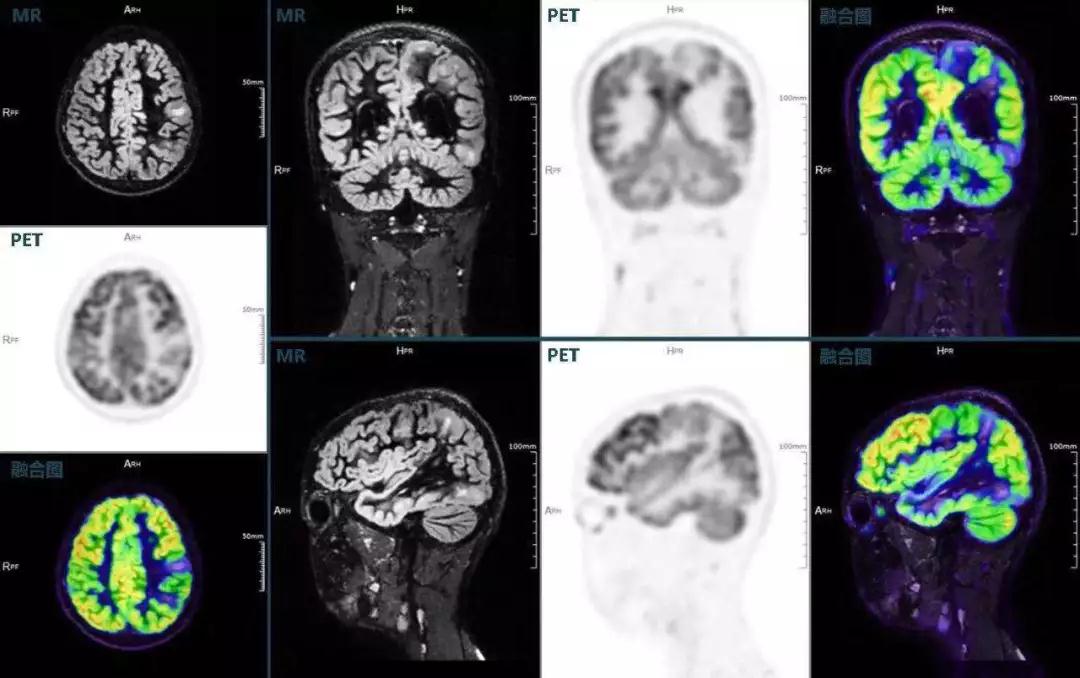

癲癇

不僅如此,聯(lián)影“時(shí)空一體”超清TOF PET/MR還搭載了大量可用于神經(jīng)疾病領(lǐng)域的高級應(yīng)用,如DIR(Double Inversion Recovery雙反轉(zhuǎn)恢復(fù))序列能夠清晰顯示大腦皮層的結(jié)構(gòu)成像,對于皮層腫脹,膠質(zhì)增生等癲癇的影像征象都能清楚呈現(xiàn);DTI(Diffusion Tensor Imaging彌散張量成像)高級應(yīng)用能夠顯示細(xì)小的神經(jīng)纖維束缺損,以更加定量的形式為醫(yī)生提供一個(gè)全新的診斷維度,輔助醫(yī)生精準(zhǔn)診斷。

(結(jié)節(jié)性硬化,MR DIR序列清晰顯示腦皮層病理改變,PET顯示了病灶區(qū)域FDG的低濃聚。PET/MR融合顯像同時(shí)提供了結(jié)構(gòu)異常改變和功能變化的信息。)